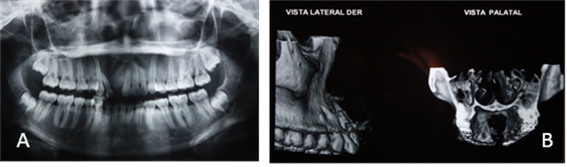

Se procede a evaluar y analizar ortopantomografia inicial, en la cual se evidencia una lesión de aproximadamente 3 cm ya que esto es referencial, evaluación de imágenes de TAC, análisis de informe imageneológico y exámenes de laboratorio, ya con todos estos datos clínicos e imageneológicos, se  procede a la discusión y planificación quirúrgica en la que se decide realizar una enucleación de la lesión y posteriormente realizar estudio histopatológico.

Figura 5. Radiografías y tomografía de haz cónico

Imagen (a) ortopantomografia (b) vista  lateral derecha y vista palatina, tomografía de haz cónico.

Figura 6. Tomografía de haz cónico.

Imagen (a) vista frontal y oclusal (b) cortes transaxiales de tomografía de haz cónico donde se evidencia tamaño y cuanto involucra los órganos dentales con una imagen hipodensa bien definida.

Figura 7. Tomografía de haz cónico.

Imágenes (a) imágenes hipodensas e hiperdensas que orientan la magnitud y volumen de la lesión (b) cortes axiales zona maxilar, con imágenes hipodensas e hiperdensas que orientan a la planificación quirúrgica.

1. De acuerdo con el objetivo específico n°1, la paciente femenina de 19 años de edad quien presenta tumor odontogénico adenomatoide acude a consulta odontológica en donde se evidencia en sus manifestaciones clínicas un aumento de volumen en el sector antero superior, con presencia de movilidad dentaria en unidades: 11, 12, 13. Al examen radiográfico se puede observar un ensanchamiento de ligamento periodontal, así como un desplazamiento de las raíces de las unidades dentarias: 12, 13.

1. En respuesta al objetivo específico n°2 posterior a la observación clínica de la paciente femenina de 19 años de edad se le indico realizarse exámenes de laboratorio, radiografía panorámica y tomografía axial computarizada.